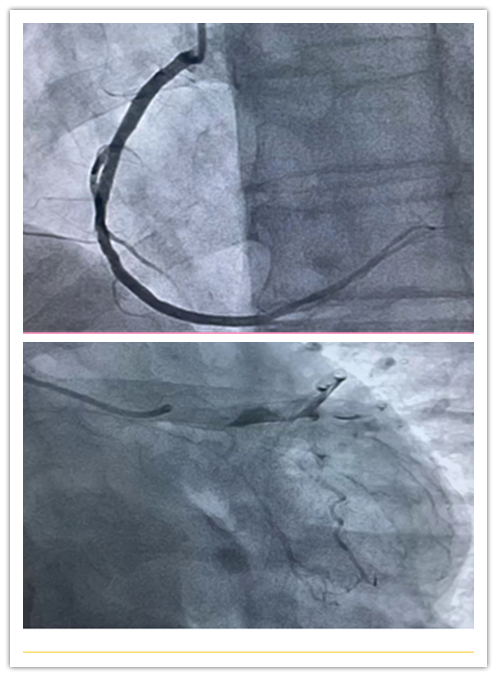

医生使用环柄注射器推入造影剂,通过X光透视可在电脑屏幕上显示血管形状。

在一路抵达目的地的过程中,医生需要通过X光透视来掌握情况,通过导管推入造影剂,这种特殊的液体可以在X光下清楚的显示血管粗细及走向,从而找到闭堵塞病变部位,也就是常说的导致血管堵塞的“罪犯血管”。